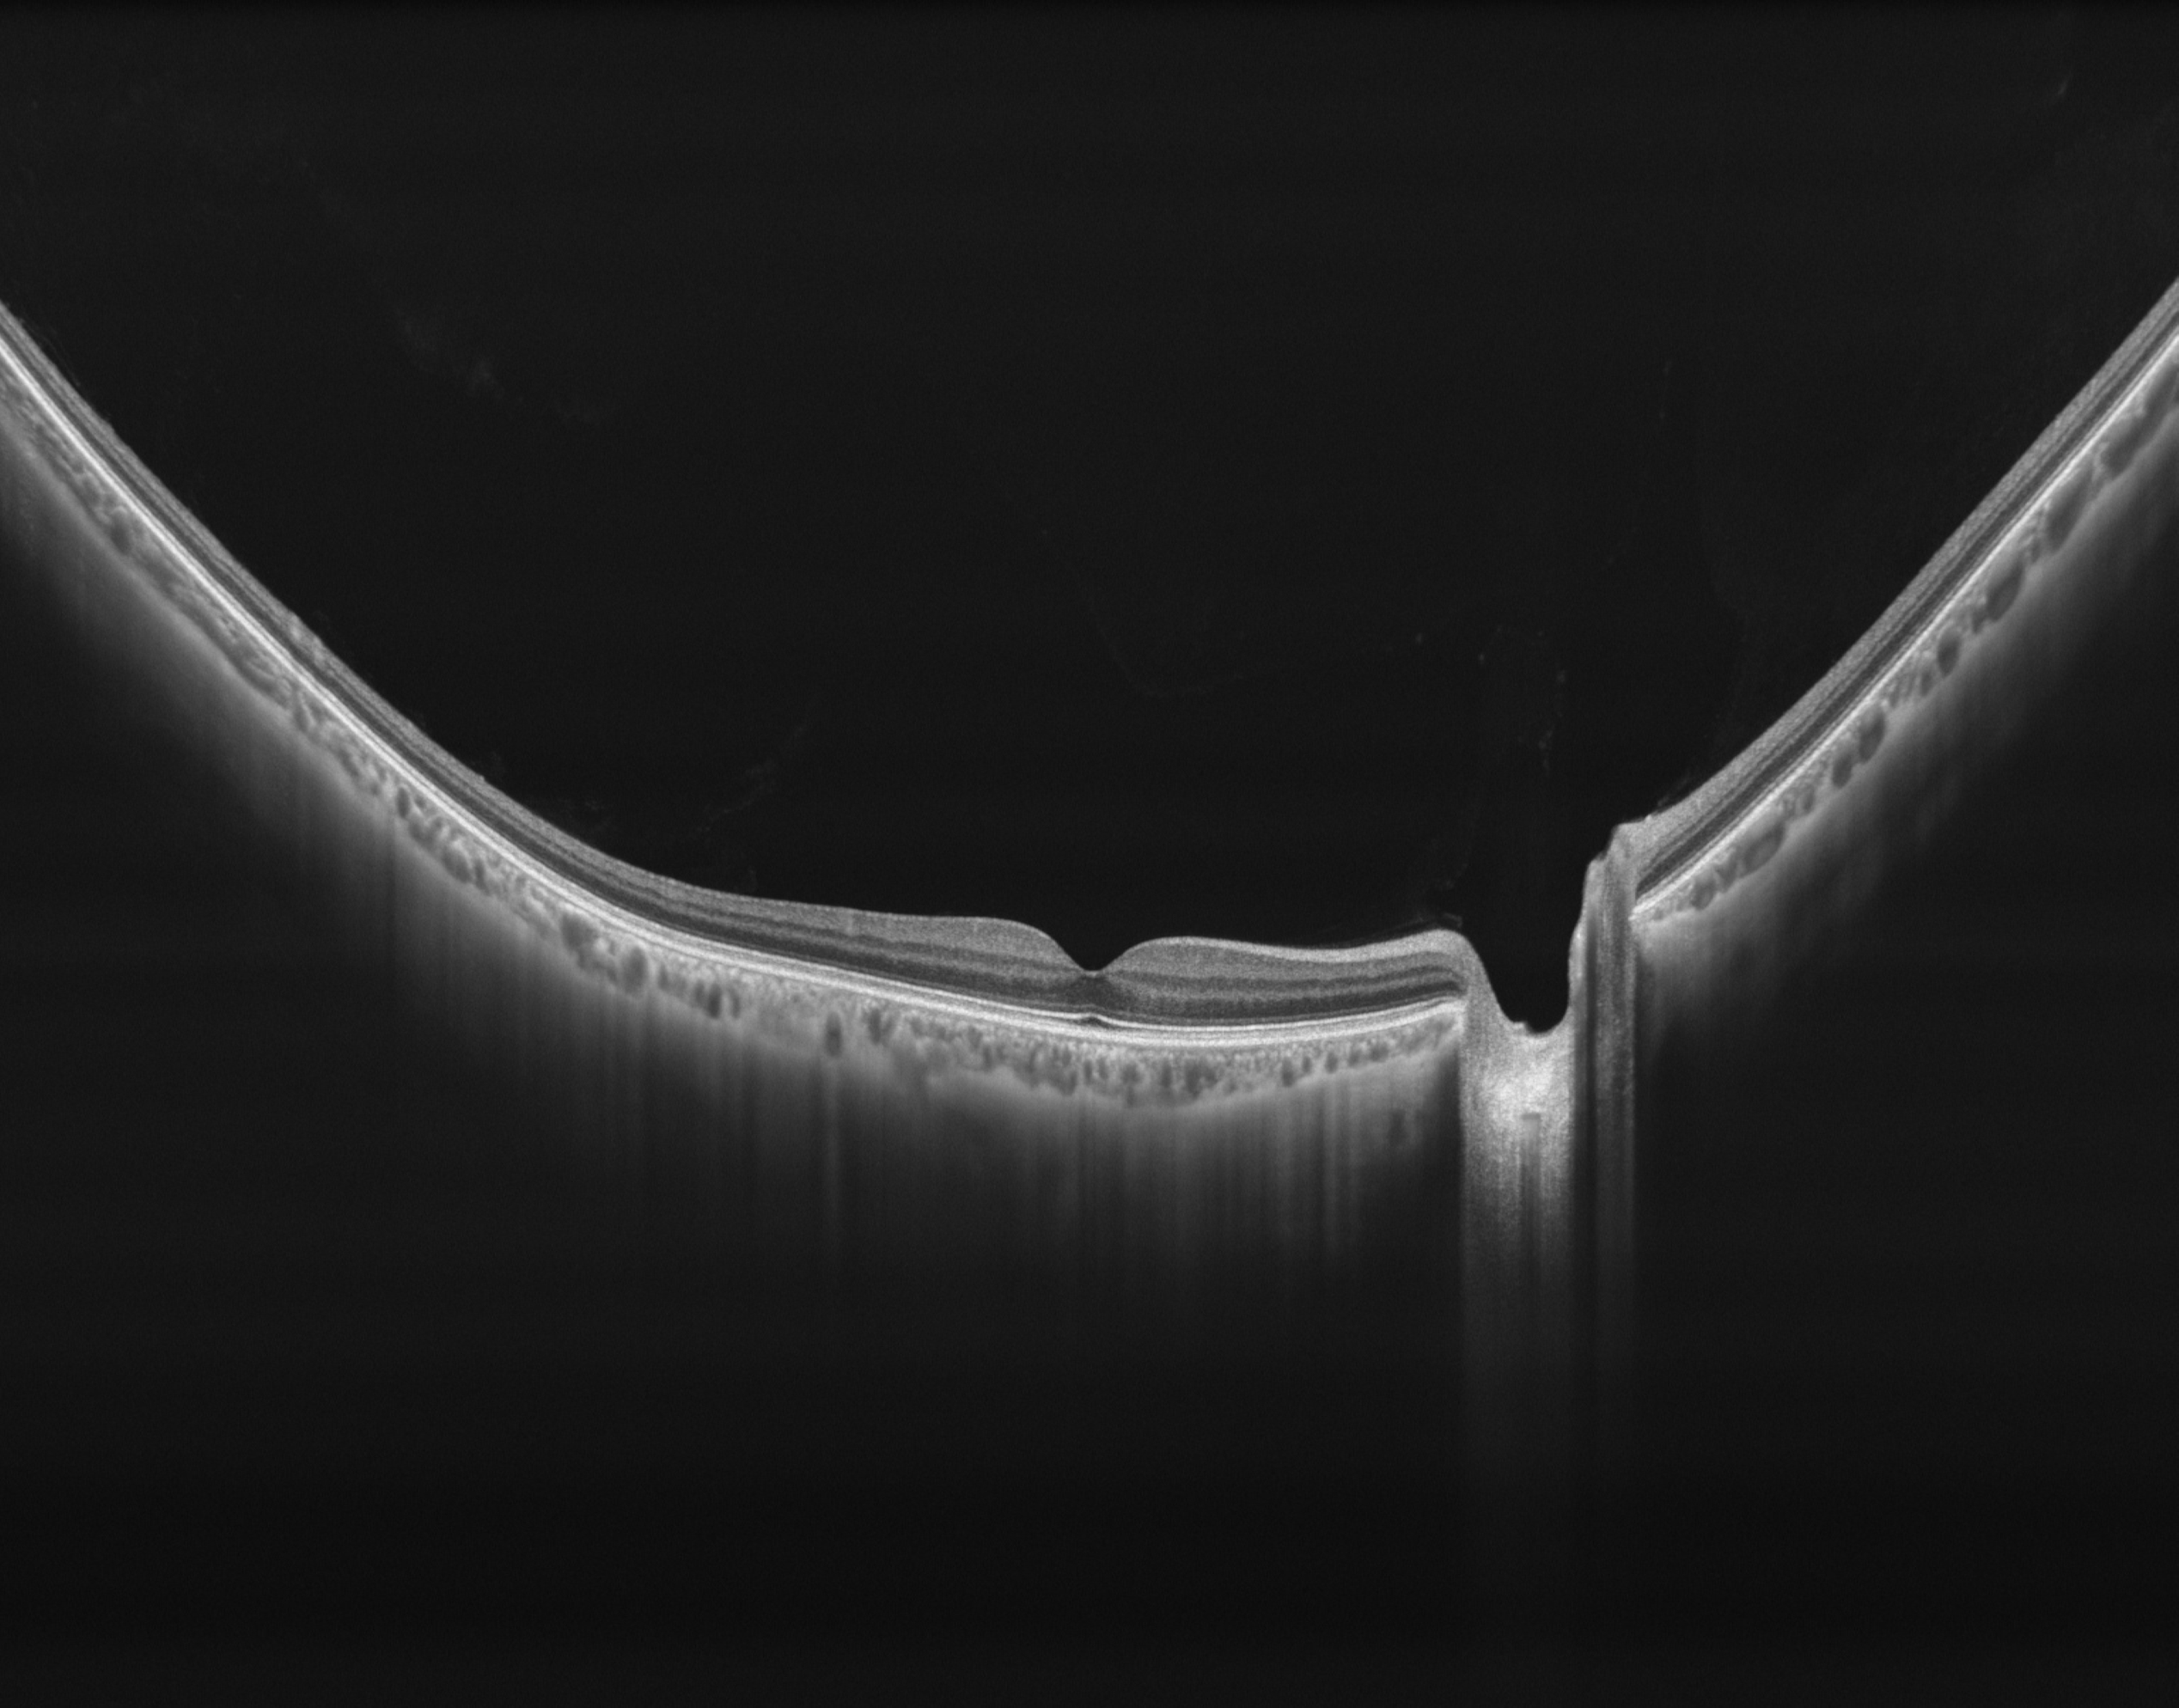

Full Range Retina OCT

- Van achterste glasvocht tot choroidea-sclera

- 24 mm tot 6 mm netvliesscan

- Automatische laagdetectie, segmentatie en meting van elke laag van het netvlies en choroïd

Voorste Oogsegment (AS) OCT

- 18mm X 6mm voorste oogsegment (AS) OCT

- Automatische metingen: CCT, ACD, LT, enz.

3D Anterior Scan